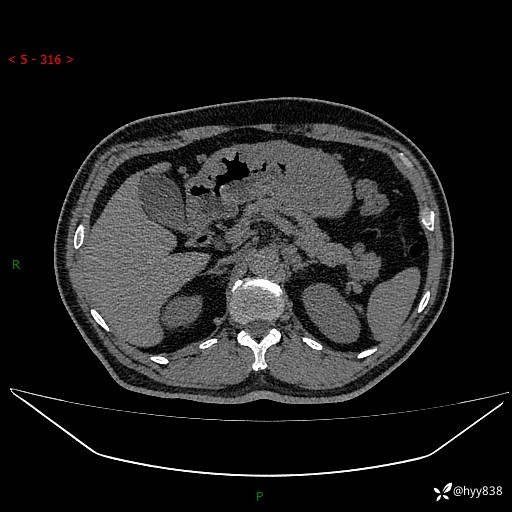

静脉期